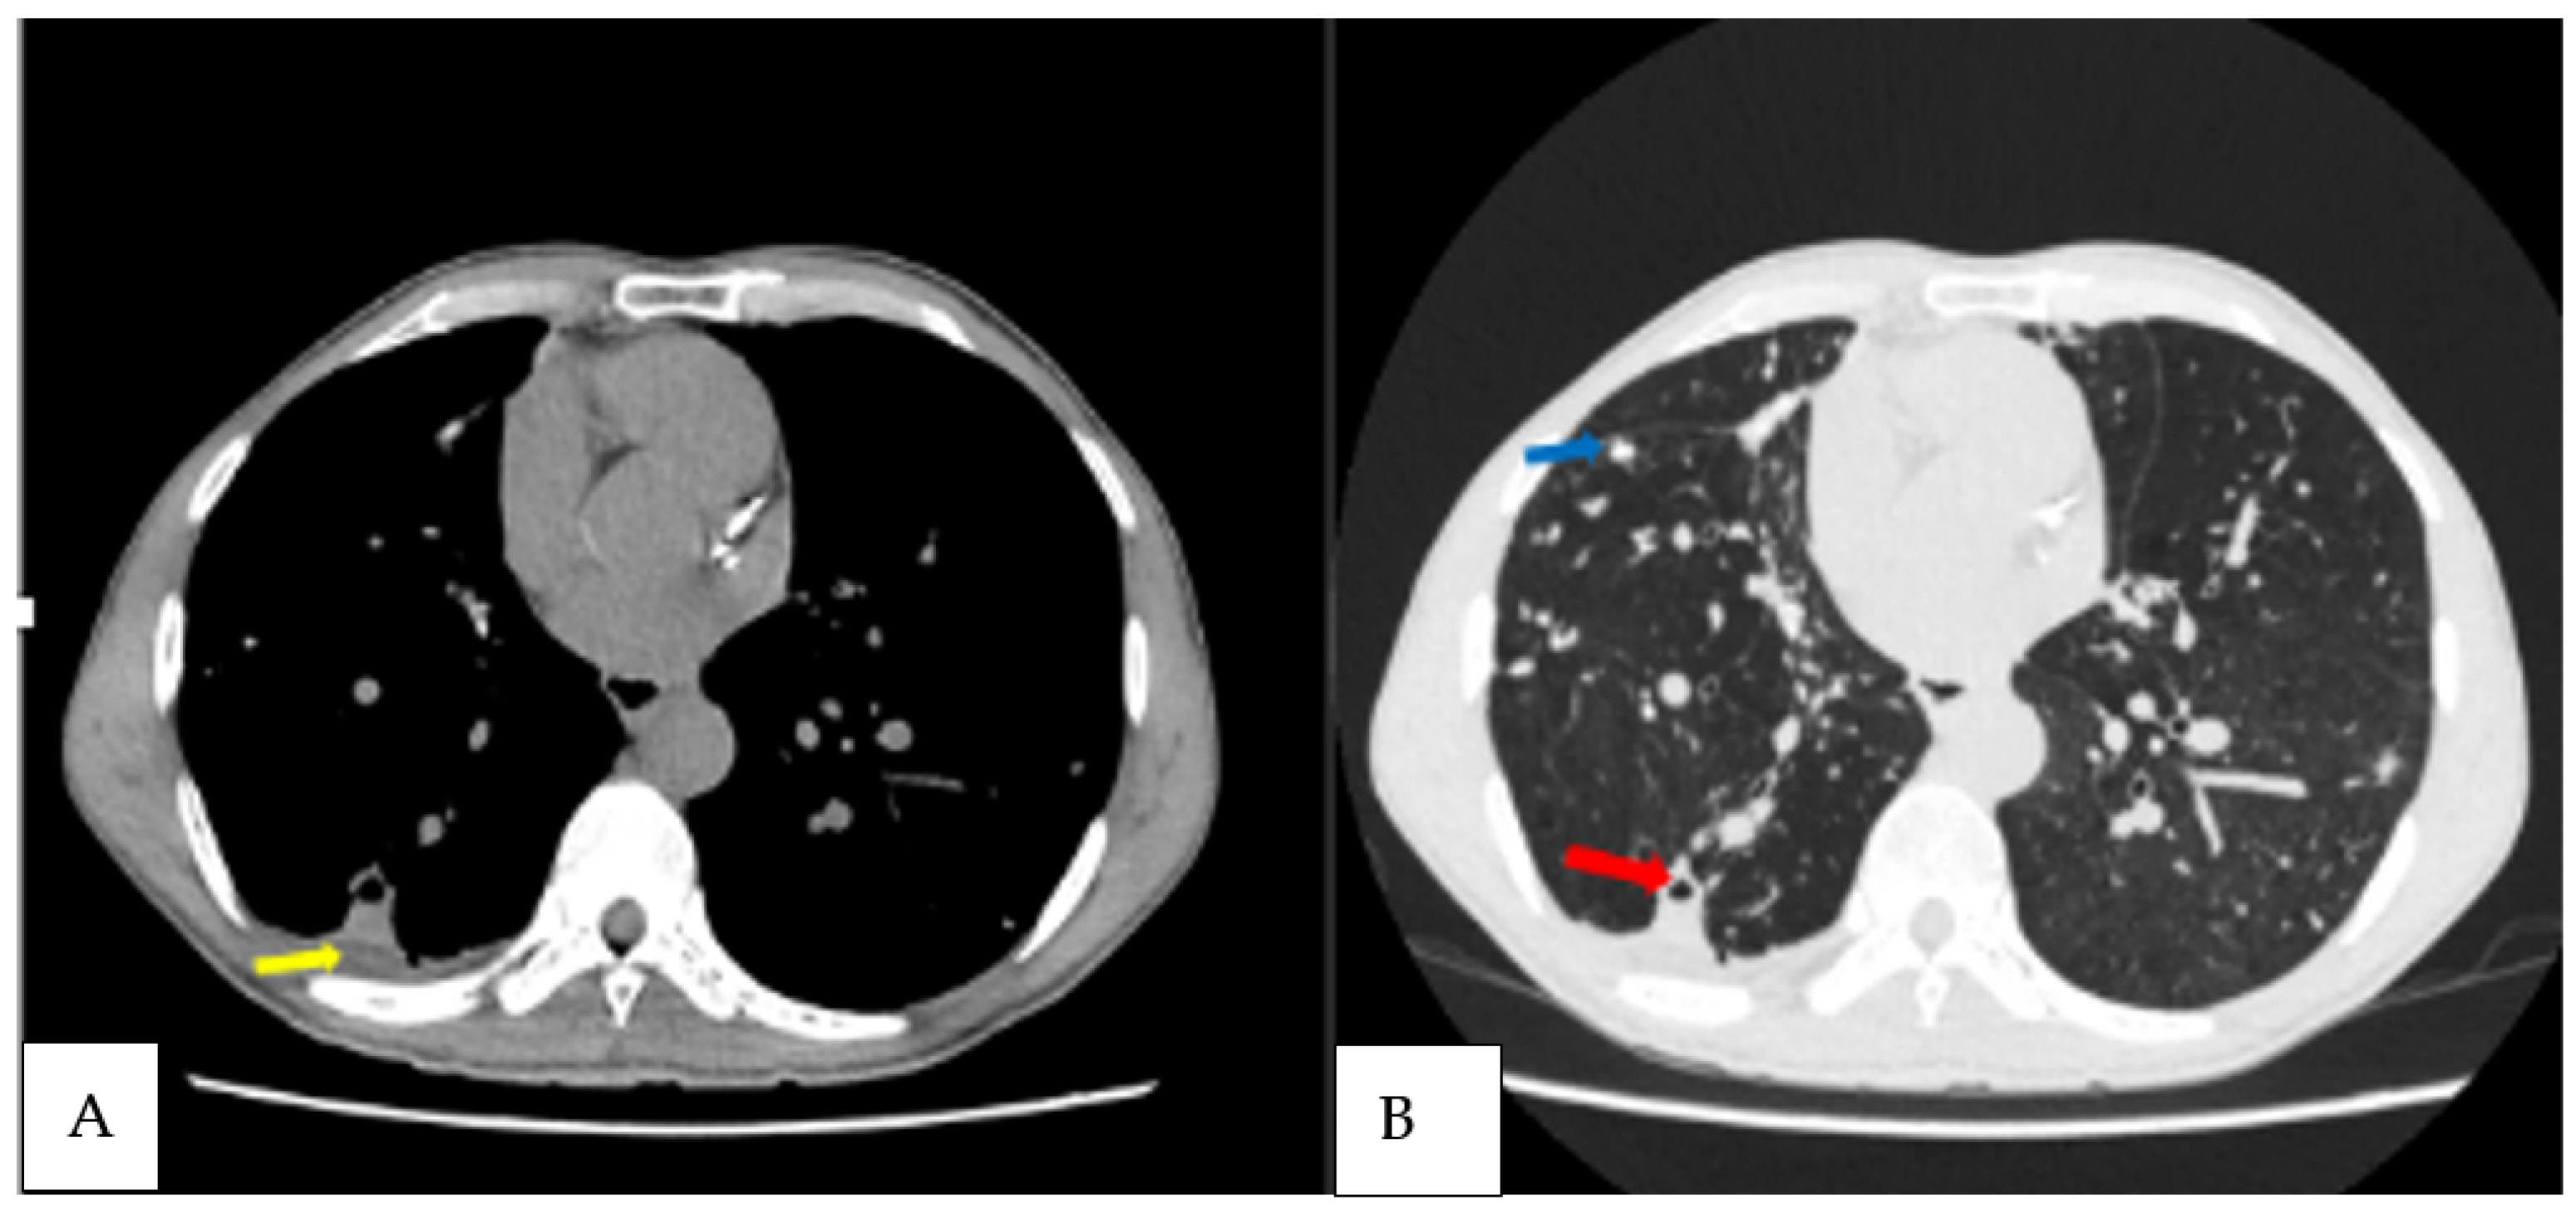

| 30 | M | Cough, haemoptysis, chest pain, weight loss | Positive | A. fumigatus, A. niger | Cavities, intracavitary material, pericavitary infiltration, pleural thickening adjacent cavity, bronchiectasis, pleural effusion | 45, 29, 83 |